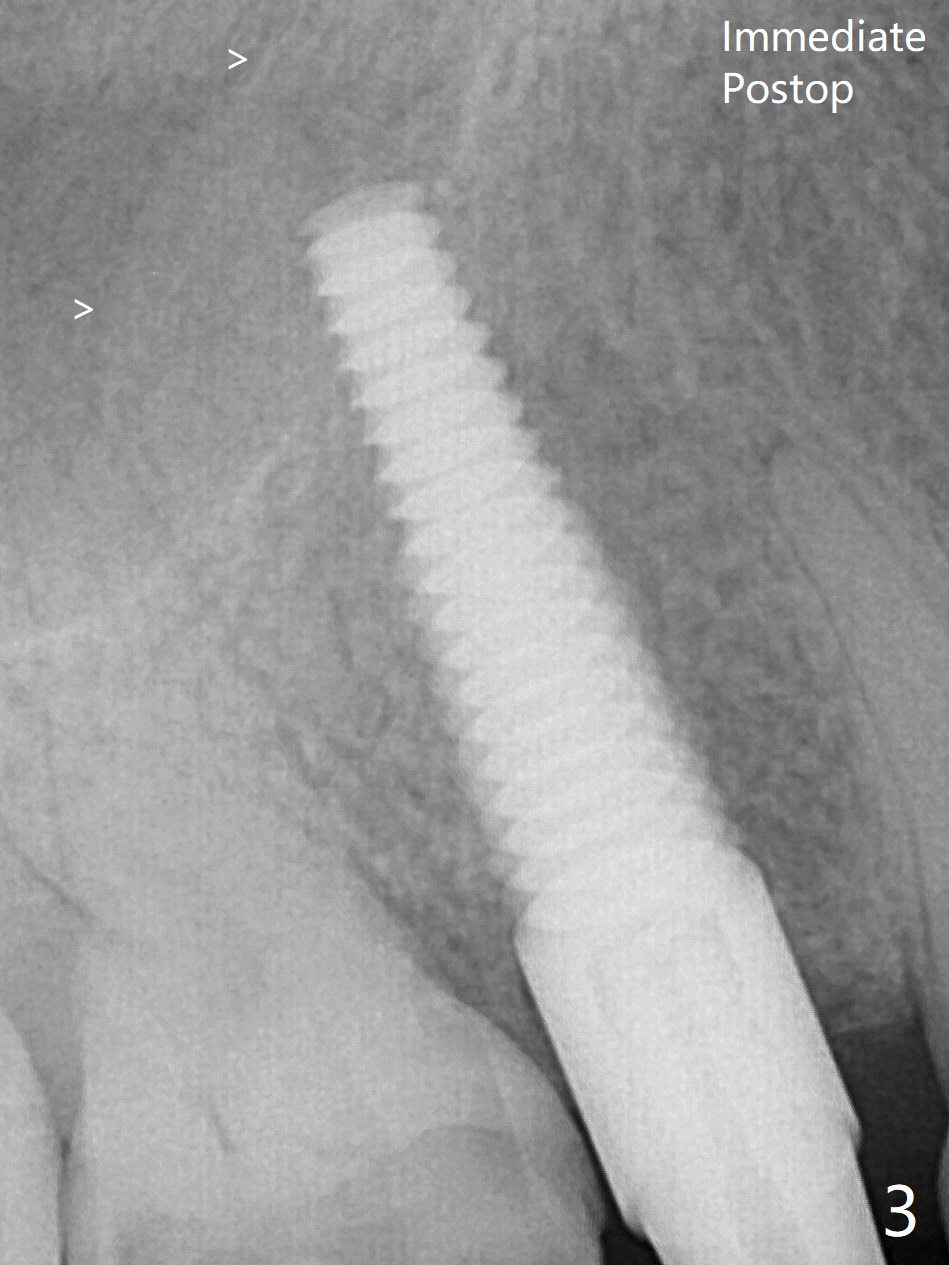

The nervous patient is not pleased with lengthened procedure and pressure from sinus lift in spite of seemingly sufficient anesthesia (Fig.3 >).  Later the implant is placed deeper ~ .5 mm for restoration.  The sinus floor appears to be thickened (Fig.4 > with apparently increased bone density), while the original sinus floor becomes indistinct 3.5 months postop.  The unipost cannot be removed for cementation.